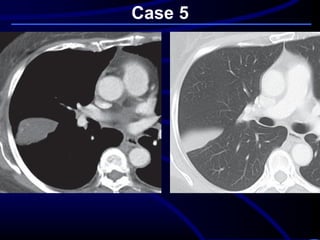

Case 5

A 68-year-old asymptomatic

nonsmoking woman underwent

preoperative screening chest

radiography in preparation for a total

knee arthroplasty. The radiographic

findings prompted subsequent chest

CT

Where is this lesion MOST

LIKELY located?

A. Lung parenchyma.

B. Mediastinum.

C. Pleura.

D. Chest wall..

What is the MOST LIKELY

diagnosis?

A. Primary lung cancer.

B. Chest wall chondrosarcoma.

C. Pseudotumor or vanishing

tumor of the pleura.

D. Localized fibrous tumor of the

pleura..